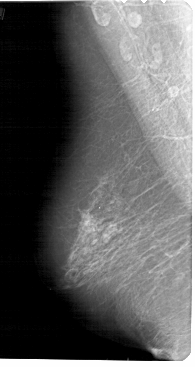

A_1457_1.RIGHT_MLO

LEFT_MLO LINES 5491 PIXELS_PER_LINE 2911 BITS_PER_PIXEL 12 RESOLUTION 43.5 NON_OVERLAY